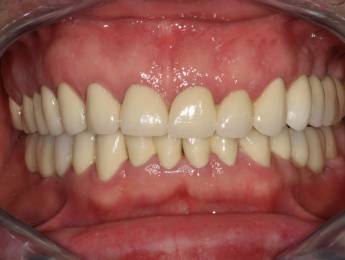

A páciens fogágybetegség miatt érkezett hozzánk. A felső fogak menthetetlen állapotban voltak. All on 6 megoldásként a felső fogak eltávolításakor 6 implantátum került beültetésre és a páciens azonnal egy fix ideiglenes hidat kapott. 4 hónapos gyógyulási idő után készült el a felső fémkerámia leplezésű körhíd.